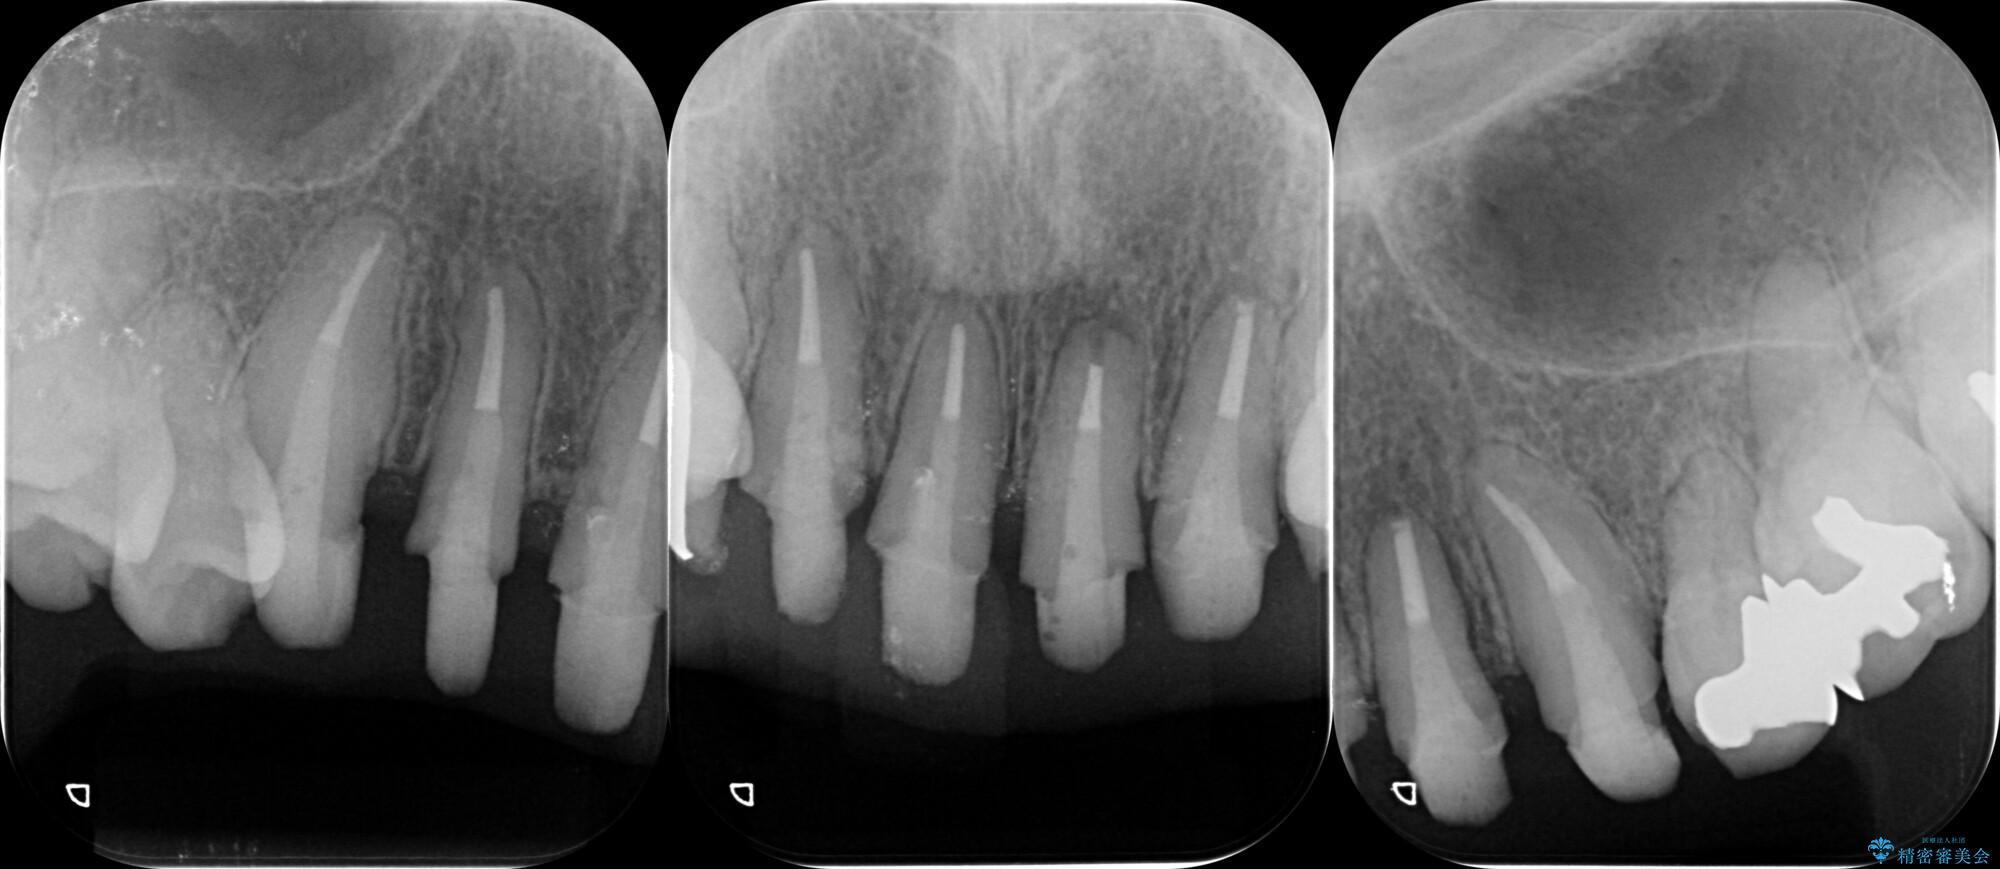

装着されていたセラミックを除去したところ、歯ぐきの奥深くまで歯牙は削られ、歯ぐきの炎症・出血が著しくみられる状態でした。

この状態で再度セラミッククラウンの作製・装着を行ってもまた同じ状態となってしまうため、歯周外科を行い歯ぐきの状態を整備したのちセラミッククラウン治療をおこなっていきます。